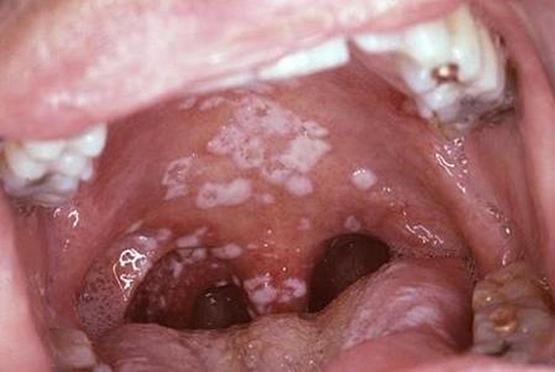

Bệnh thủy đậu gia tăng ở trẻ

Theo BS Đỗ Châu Việt - Trưởng khoa Nhiễm BV Nhi đồng 2 TP.HCM, bệnh thủy đậu đang có chiều hướng gia tăng, nhất là trẻ em. Vì thế việc...

Bệnh thủy đậu: Coi chừng lây từ… người nhà

Mới đây, Bệnh viện Nhi Đồng 1 đã tiếp nhận một bệnh nhi 15 tháng tuổi bị lây thủy đậu từ mẹ....